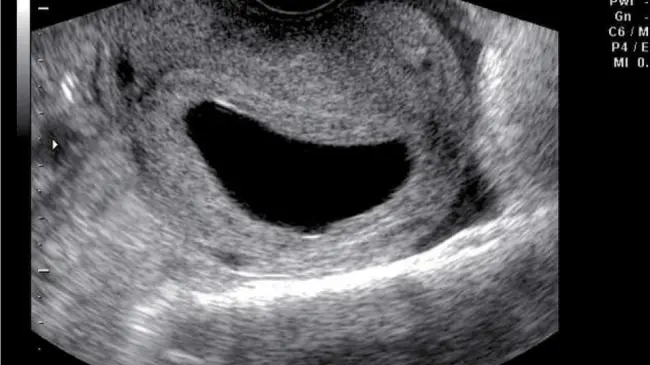

SANTO DOMINGO.- Llegar a las seis semanas de embarazo significa que ya los latidos del bebé pueden verse a través de un eco intravaginal, según la doctora Lilliam Fondeur.

Sin embargo, pueden darse casos en que la mujer puede tener un saco anembrionado, lo que significa que no hay un embrión dentro del mismo.

Fondeur explica que si entre las semanas 7 a 8 si no se figura un embrión es porque no hay embarazo.